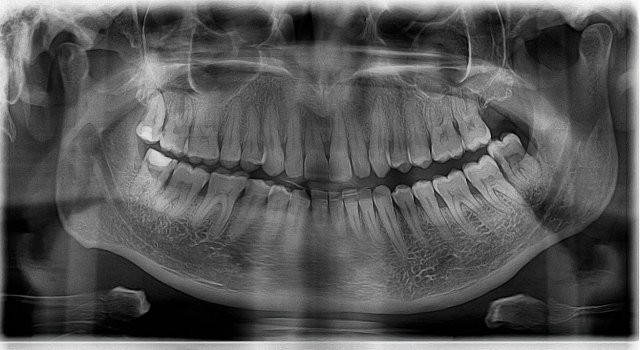

Ako ste ikada imali nesreću da izgubite zub, možda ste u prošlosti razmišljali o zubnim implantatima. Možda ste se takođe iznenadili kada ste saznali koliko su skupi i da se često koriste materijali kao što su živa ili srebro. Ali šta ako bi naši zubi zaista mogli da izrastu? Na sreću, postoji neverovatno otkriće u oralnom zdravlju koje bi moglo potpuno da promeni odnos prema ovom problemu.